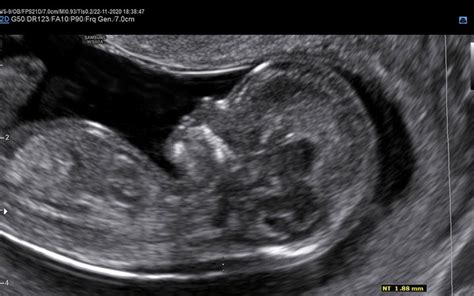

Nuhalna svetlina, strokovno imenovana nuhalna translucenca (NT), je predel zunajcelične tekočine, ki se nahaja na zatilju ploda. Na ultrazvočni sliki je to področje vidno kot svetlejši sloj, omejen s črto, ki je svetlejša od okoliške tekočine. Sama debelina nuhalne svetline je ključen parameter pri oceni tveganja. Višja kot je izmerjena vrednost nuhalne svetline, povečano je nabiranje tekočine na plodovem zatilju. To povečano nabiranje tekočine je pogosto posledica slabšega razvoja limfatičnega sistema ploda in je statistično povezano z večjim tveganjem za določene kromosomske napake. Med najbolj pogostimi so Downov sindrom (trisomija 21. kromosoma), Edwardsov sindrom (trisomija 18. kromosoma) in Patauov sindrom (trisomija 13. kromosoma). Poleg tega lahko širša nuhalna svetlina nakazuje tudi večje tveganje za druge razvojne nepravilnosti, predvsem srčne napake. V primeru, ko je izmerjena debelina nuhalne svetline nad 3,5 mm, je zelo priporočen podroben pregled plodovega srca v drugem trimesečju nosečnosti.

Preiskava nuhalne svetline je časovno zelo specifična in se izvaja med 11 0/7 in 13 6/7 tednom nosečnosti. To obdobje ustreza dolžini ploda med 45 in 84 mm (razdalja teme-trtica, CRL). Preiskava je mogoča tudi pri nosečnicah s dvojčki. Običajno se izvaja z ultrazvočnim tipalom preko trebuha (transabdominalni ultrazvok). V primeru slabše preglednosti ali neugodnega položaja ploda pa se lahko uporabi transvaginalno tipanje. Pred samo preiskavo je nosečnico naprošena, da popolnoma izprazni sečni mehur, kar omogoča boljšo vizualizacijo. Natančnost meritve je odvisna od pravilne lege ploda, zato se lahko čas trajanja pregleda med posameznimi nosečnicami razlikuje. V Sloveniji je pregled nuhalne svetline za nosečnice, mlajše od 35 let, v veliki meri samoplačniški, s ceno, ki se giblje med 60 in 100 EUR. Vendar pa se od leta 2023 storitev nuhalne svetline krije s strani Zavoda za zdravstveno zavarovanje Slovenije (ZZZS) za vse nosečnice, neodvisno od starosti. Za izvedbo pregleda ni potrebna napotnica. Pomembno je, da pregled opravi ginekolog z veljavno licenco fundacije FMF (Fetal Medicine Foundation), kar zagotavlja ustrezno kakovost meritev.